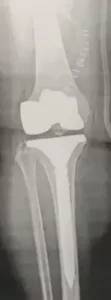

- خشونة الركبة (التهاب المفاصل التنكسي).

- عمليات تغيير مفصل الركبة بالكامل أو جزئياً.